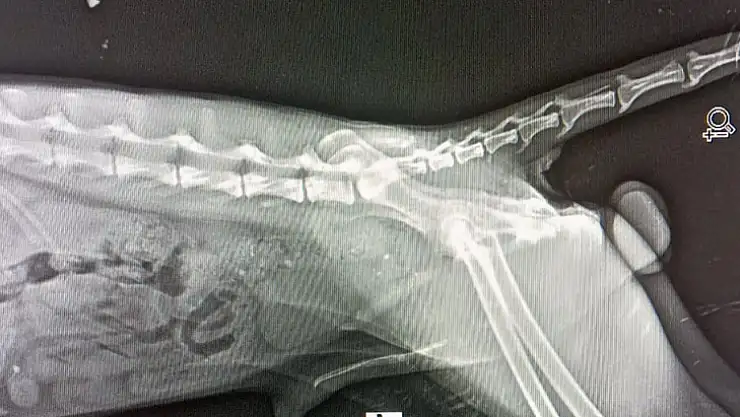

Yaralı tilkinin çekilen filminde arka ayaklarından yaralı olduğu ortaya çıktı. Müşahade altında tutulan Tikinin durumunun stabil hale getirilerek izlendiği açıklandı. Datça DKMP Şefliği, bu sürece katkısı olan tüm gönüllü hayvan severlere teşekkür etti.